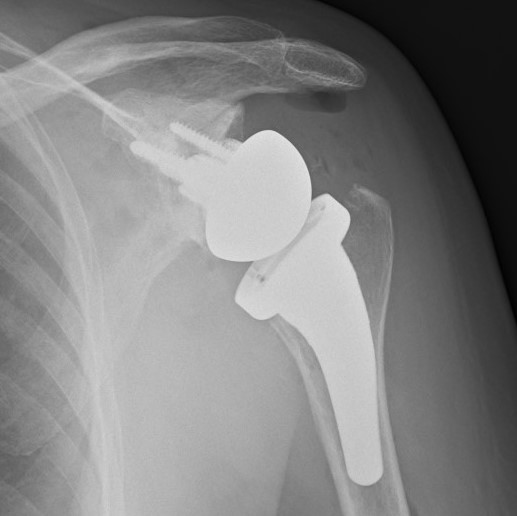

Operative: If there has been no improvement with physiotherapy then a shoulder replacement can be carried out. The exact type of replacement surgery depends on x-ray findings and the state of the rotator cuff tendon. In most situations, the ball and socket are replaced.